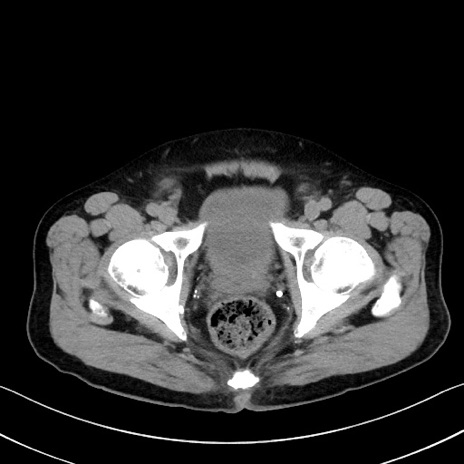

症例35(横断像)

【症例】70歳代 男性

【主訴】腹部膨満、嘔吐

【現病歴】昨日より腹部膨満感出現。本日増悪し、仙痛出現。嘔吐あり、受診。

【既往歴】糖尿病、胆摘後

【身体所見】BP 149/80mmHg、HR 74/min、BT 35.9℃、腹部:膨満、軟、圧痛なし。腸雑音減弱あり。上腹部正中切開瘢痕あり。

【データ】WBC 13500、CRP 1.72